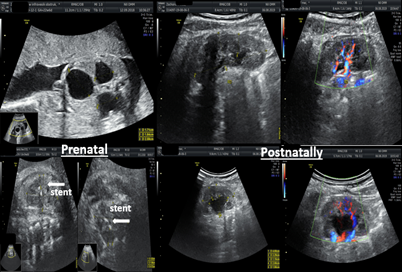

Figure 5 A variant of bilateral nephroamniotic shunting in PUV disorder.

Figure 5,6 shows a case of bilateral nephroamniotic shunting surgery with the "SDE-MED" stent in case of PUV. Stent expulsions were not observed. Shunting surgery of the left fetal kidney was performed at 22 weeks of pregnancy, after 500 ml of amnioinfusion, and the shunting surgery of the right kidney was performed at 24 weeks of pregnancy. During the first procedure of intrauterine shunting, there was pronounced oligohydramnios, and the amniotic fluid index was equal to 4 cm, which required amnioinfusion in the volume of 500 ml. Indications for shunting surgery of the right kidney were grade III hydronephrosis, which did not stop after shunting surgery on the left kidney. Postnatally, the function of both kidneys was preserved. After surgical correction of the PUV disorder, the patient currently has pyelectasia in the left kidney.